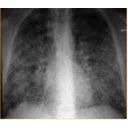

Rx histoplasmosis.jpg